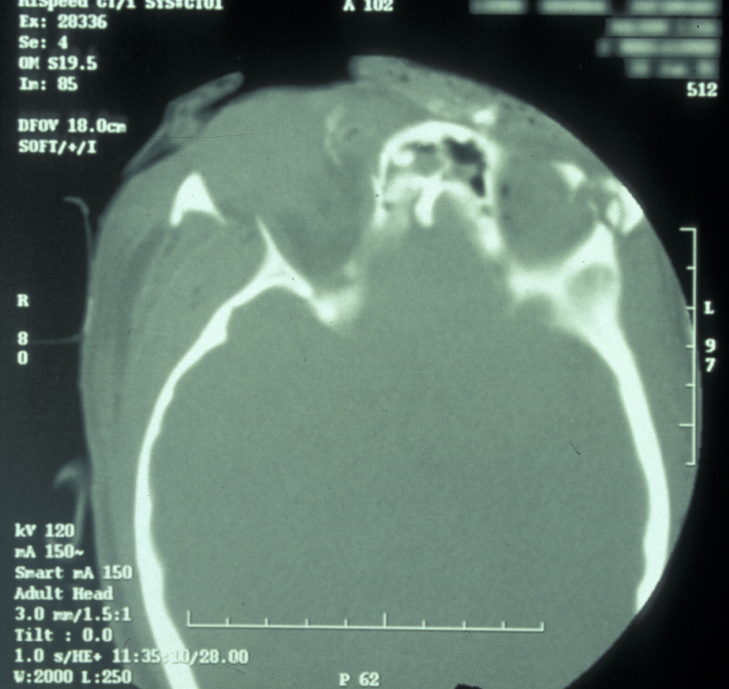

Plain film X-ray radiographs from different angles (occipitomental views) give some information, but a much more accurate assessment of the extent of the fracture can be obtained from CT scans (see Figure 11 for an example).

Figure 11: CT scan of a midface fracture.